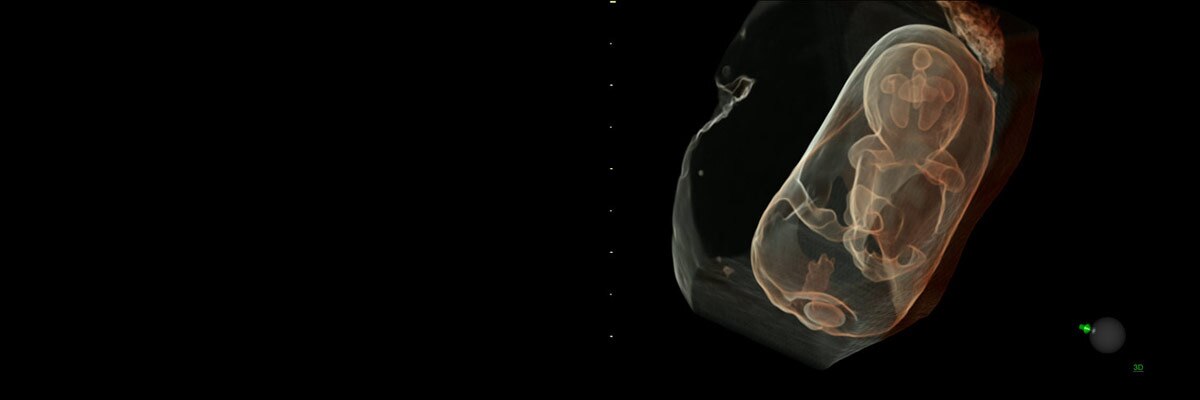

製品詳細 | 村中医療器株式会社 | HUNTLEIGH 胎児超音波心音計, 妊娠初期胎児 - Voluson E10 - Voluson - 超音波 - 製品 | GE,

妊娠初期胎児 - Voluson E10 - Voluson - 超音波 - 製品 | GE, 妊娠初期胎児 - Voluson E10 - Voluson - 超音波 - 製品 | GE,